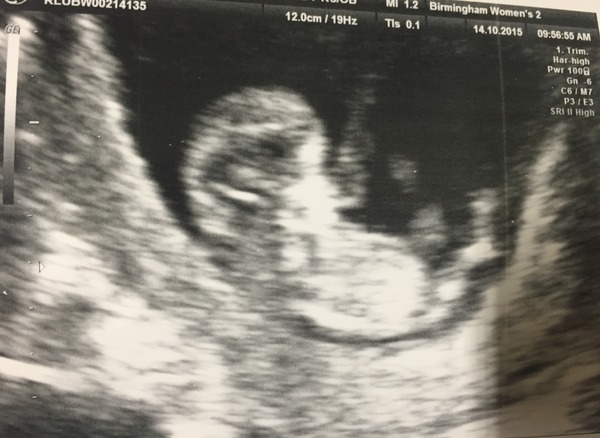

Lovely scan pictures Billy and Frozen they're both such good pictures.

Great scan pictures!

That's a fab scan pic frozen love seeing these pics :)

It's lovely to see other people's scans, keep them coming!

Congrats, Hoopoe. What a lovely scan.

Love your scan too, frozen.

Hoop that's a lovely scan pic! :) ooooh I'm excited just a week tomorrow until mine!!!